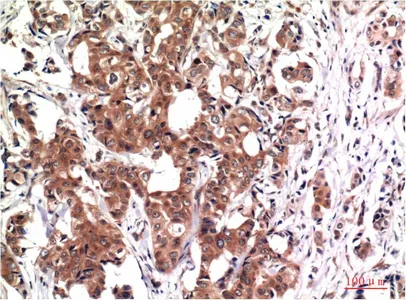

GSK3 beta (9F9) Mouse Monoclonal Antibody

Cat: AMM03603

GSK3 beta (9B1) Mouse Monoclonal Antibody

Cat: AMM03604

GSK3 beta (4C4) Mouse Monoclonal Antibody

Cat: AMM03605